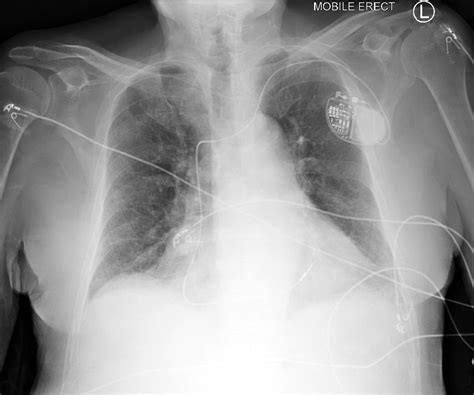

To obtain an accurate Pulmonary Edema Cxr, technical factors must be optimized. Portable bedside chest X-rays, common in critical care settings, are often performed in an anteroposterior (AP) projection. This projection can artificially magnify the heart size, making it difficult to differentiate mild cardiomegaly from normal variants. Therefore, standardized positioning is vital for consistent interpretation.

High-quality images allow for the visualization of delicate structures such as the fissures. Increased fluid in the interlobar fissures, known as a "fissural thickening," is another reliable indicator of interstitial pulmonary edema. Furthermore, the quality of inspiration affects the appearance of the lung fields; poor inspiration can create an artificial appearance of crowding of the bronchovascular markings, potentially mimicking mild congestion.

Clinical Management and Monitoring

Once the Pulmonary Edema Cxr confirms the diagnosis, management usually involves the administration of loop diuretics, vasodilators, and oxygen therapy. The imaging serves as a baseline to monitor the patient's response to therapy. Following treatment, a repeat chest X-ray is often ordered to observe the "clearing" of the lung fields, which usually occurs as the patient achieves a negative fluid balance.

Persistent opacities despite adequate diuresis may suggest complications such as pneumonia, lung collapse, or a non-cardiogenic component to the pulmonary edema. Regular assessment through imaging ensures that the treatment plan is effectively targeting the underlying cause of the fluid overload.